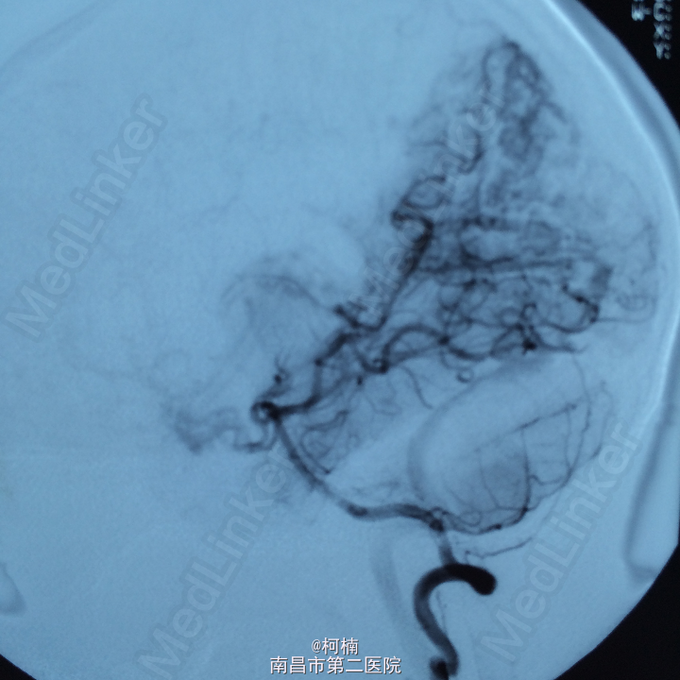

查体:神志朦胧,颈抵抗,右侧肢体及躯干深感觉减退,左侧正常。 辅助检查:复查CT提示左侧额叶出血破入脑室系统

诊断:脑动静脉畸形 处理:予急诊行DSA检查,提示脑动静脉畸形,予行血管内栓栓塞治疗